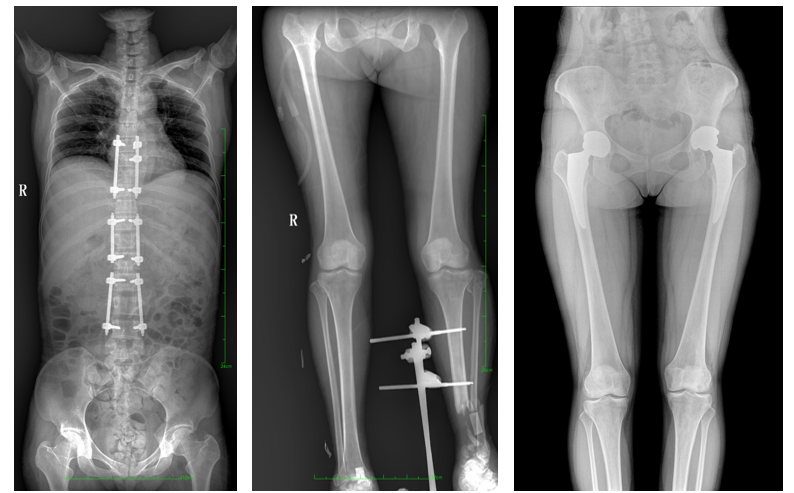

DR常用于人體胸部及骨骼攝片,也可拍攝其他部位,例如腹部、牙齒、頭顱等。使用人群較廣,可以進行全身各部位檢查,曝光后幾秒就可獲得數字影像,成像速度快,且價格便宜,極大提高了工作效率,方便臨床重癥、急癥患者的診治。

站立位X線影像是測定人體負重骨骼的生物學力線、對稱結構平滑線及脊柱側凸角等首選的檢查內容,這和CT、MRI臥位成像,在臨床意義上有著根本區別。在脊柱及下肢的臨床治療過程中,一般需要進行矯正和關節置換手術治療,在對其進行手術前后,均需要拍攝站立位負重X光片以便分析病情,明確診斷和觀察治療效果。

常規DR拍攝面積有限,最大規格僅有43cm,但成人男性全脊柱長度平均為70-75cm,女性為66-70cm,而雙下肢更長。普愛醫療PLX8600動態DR的43cm*86cm超大有效視野,可一次成像全脊柱及雙下肢。